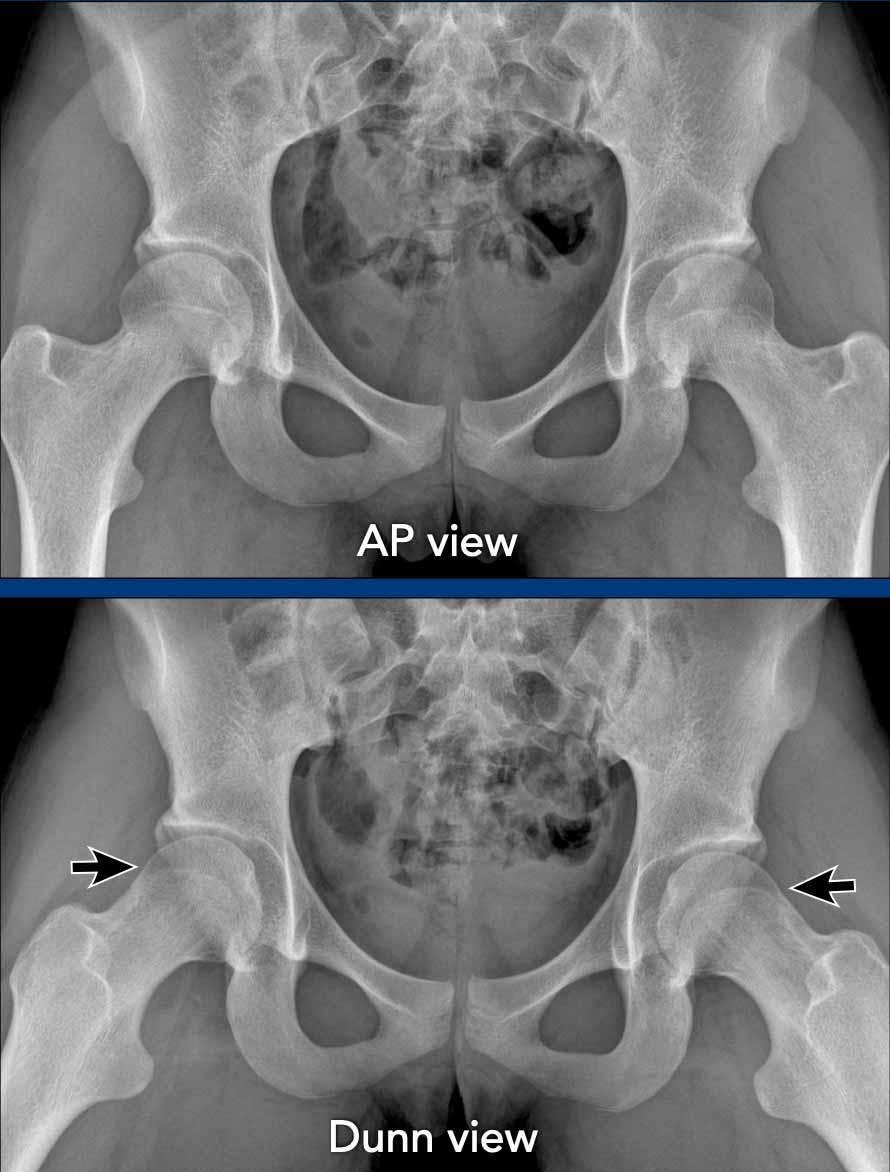

AP and Dunn view

Tư thế thẳng (AP)

Tư thế chụp trước-sau (AP) của khung chậu đóng vai trò quan trọng trong việc xác định các bất thường xương, đánh giá khe khớp, đo các góc quan trọng và xác định sự thẳng trục tổng thể của khung chậu, tất cả đều góp phần vào chẩn đoán hội chứng xung đột khớp háng-ổ cối.

Tuy nhiên, tư thế này thường được sử dụng kết hợp với các tư thế chụp khác để đánh giá toàn diện hơn.

Tư thế Dunn

Tư thế Dunn là tư thế chụp nghiêng giúp hiển thị rõ vùng tiếp nối chỏm-cổ xương đùi theo góc độ thường không thấy được trên các tư thế tiêu chuẩn như tư thế thẳng trước-sau (AP) hoặc tư thế nghiêng. Tư thế này được thực hiện bằng cách cho bệnh nhân nằm ngửa với háng bên tổn thương gấp khoảng 45° và dạng 20° đến 30° ở tư thế xoay trung tính.

Tư thế này cho phép quan sát rõ hơn mặt trên-trước của vùng tiếp nối chỏm-cổ xương đùi, vốn thường khó đánh giá trên các tư thế tiêu chuẩn và là vị trí hay gặp nhất của biến dạng dạng cam.

Hình ảnh

Vận động viên thể dục dụng cụ 20 tuổi với các triệu chứng ở hông.

Trên phim chụp AP, vùng đầu-cổ xương đùi trông bình thường.

Trên phim chụp tư thế Dunn, có hình thái Cam ở cả hai bên (mũi tên).